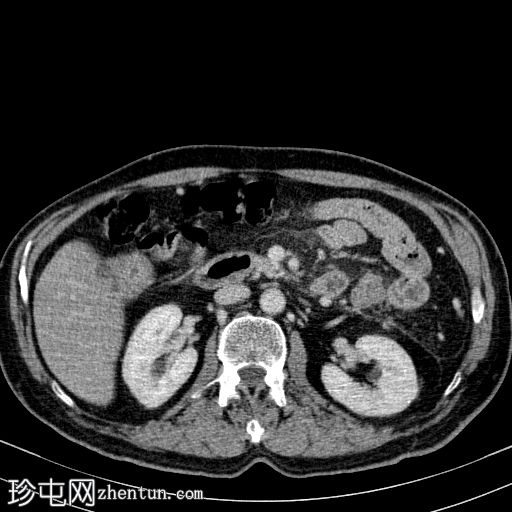

轴向C+动脉期

胰体尾弥漫性增大,特征为胰腺实质低强化,无明显坏死区域。

该病灶与以下表现相关:

胰周筋膜平面边界不清的污迹,无明显壁形成、气室、固体碎片或血液产物。

多个亚厘米大小、非特异性的腹主动脉旁淋巴结和肠系膜淋巴结,可能具有反应性。

病变范围如下:

病变横向延伸至左前肾旁间隙,伴有Gerota筋膜增厚。

病变向下延伸至盆腔。

无肠系膜或脾脏血管阻塞的证据。

未见导管扩张或钙化。